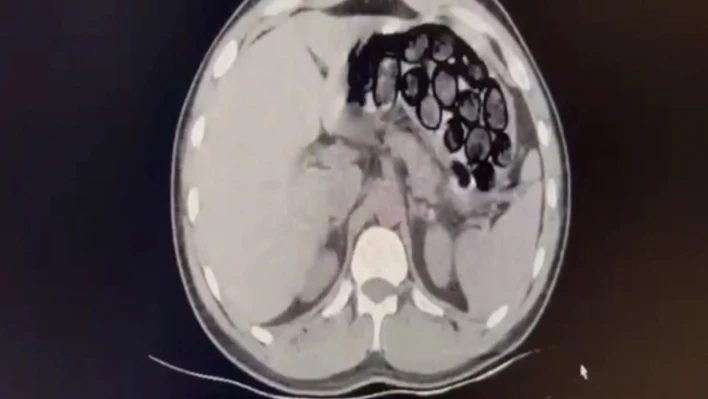

Jandarma ekiplerince takibe alınan İranlı şahıs ve beraberindeki 2 kişi, Kars’ın Selim ilçesi girişinde ticari takside yakalandı. Yapılan üst aramasında bir şey bulunamayan Omid Baghernezad, Kars Harakani Devlet Hastanesi’ne götürüldü. Burada çekilen röntgende Omid Baghernezad’ın mide ve bağırsağında kapsüller halinde 65 parça halinde 412 gram sentetik uyuşturucu olduğu belirlendi.